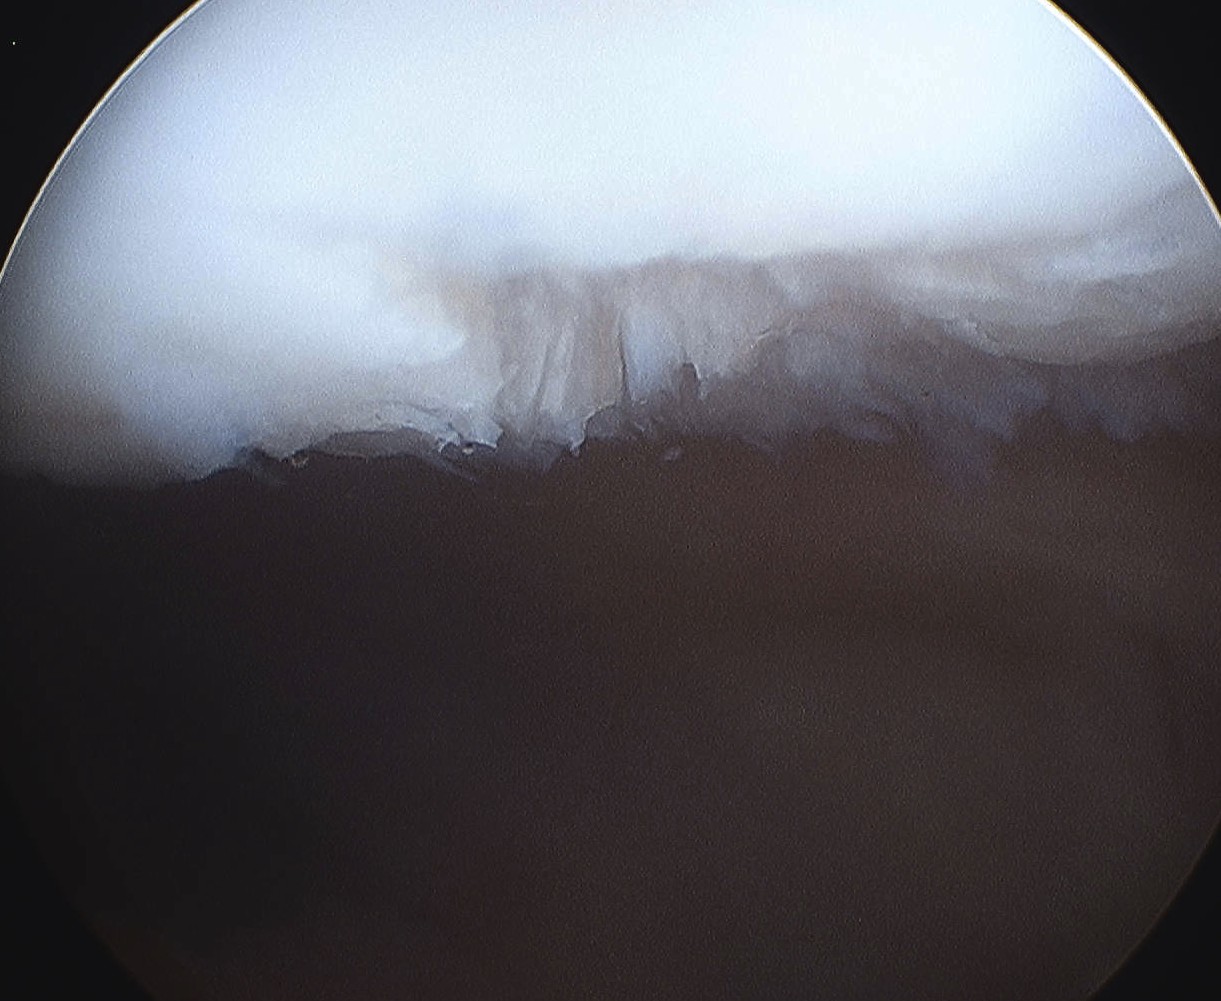

Fat Pad Syndrome

Hoffa's syndrome

- impingement of the fat pad with knee ROM

Theory

May be more prevalent in patients with intact ligamentum mucosum